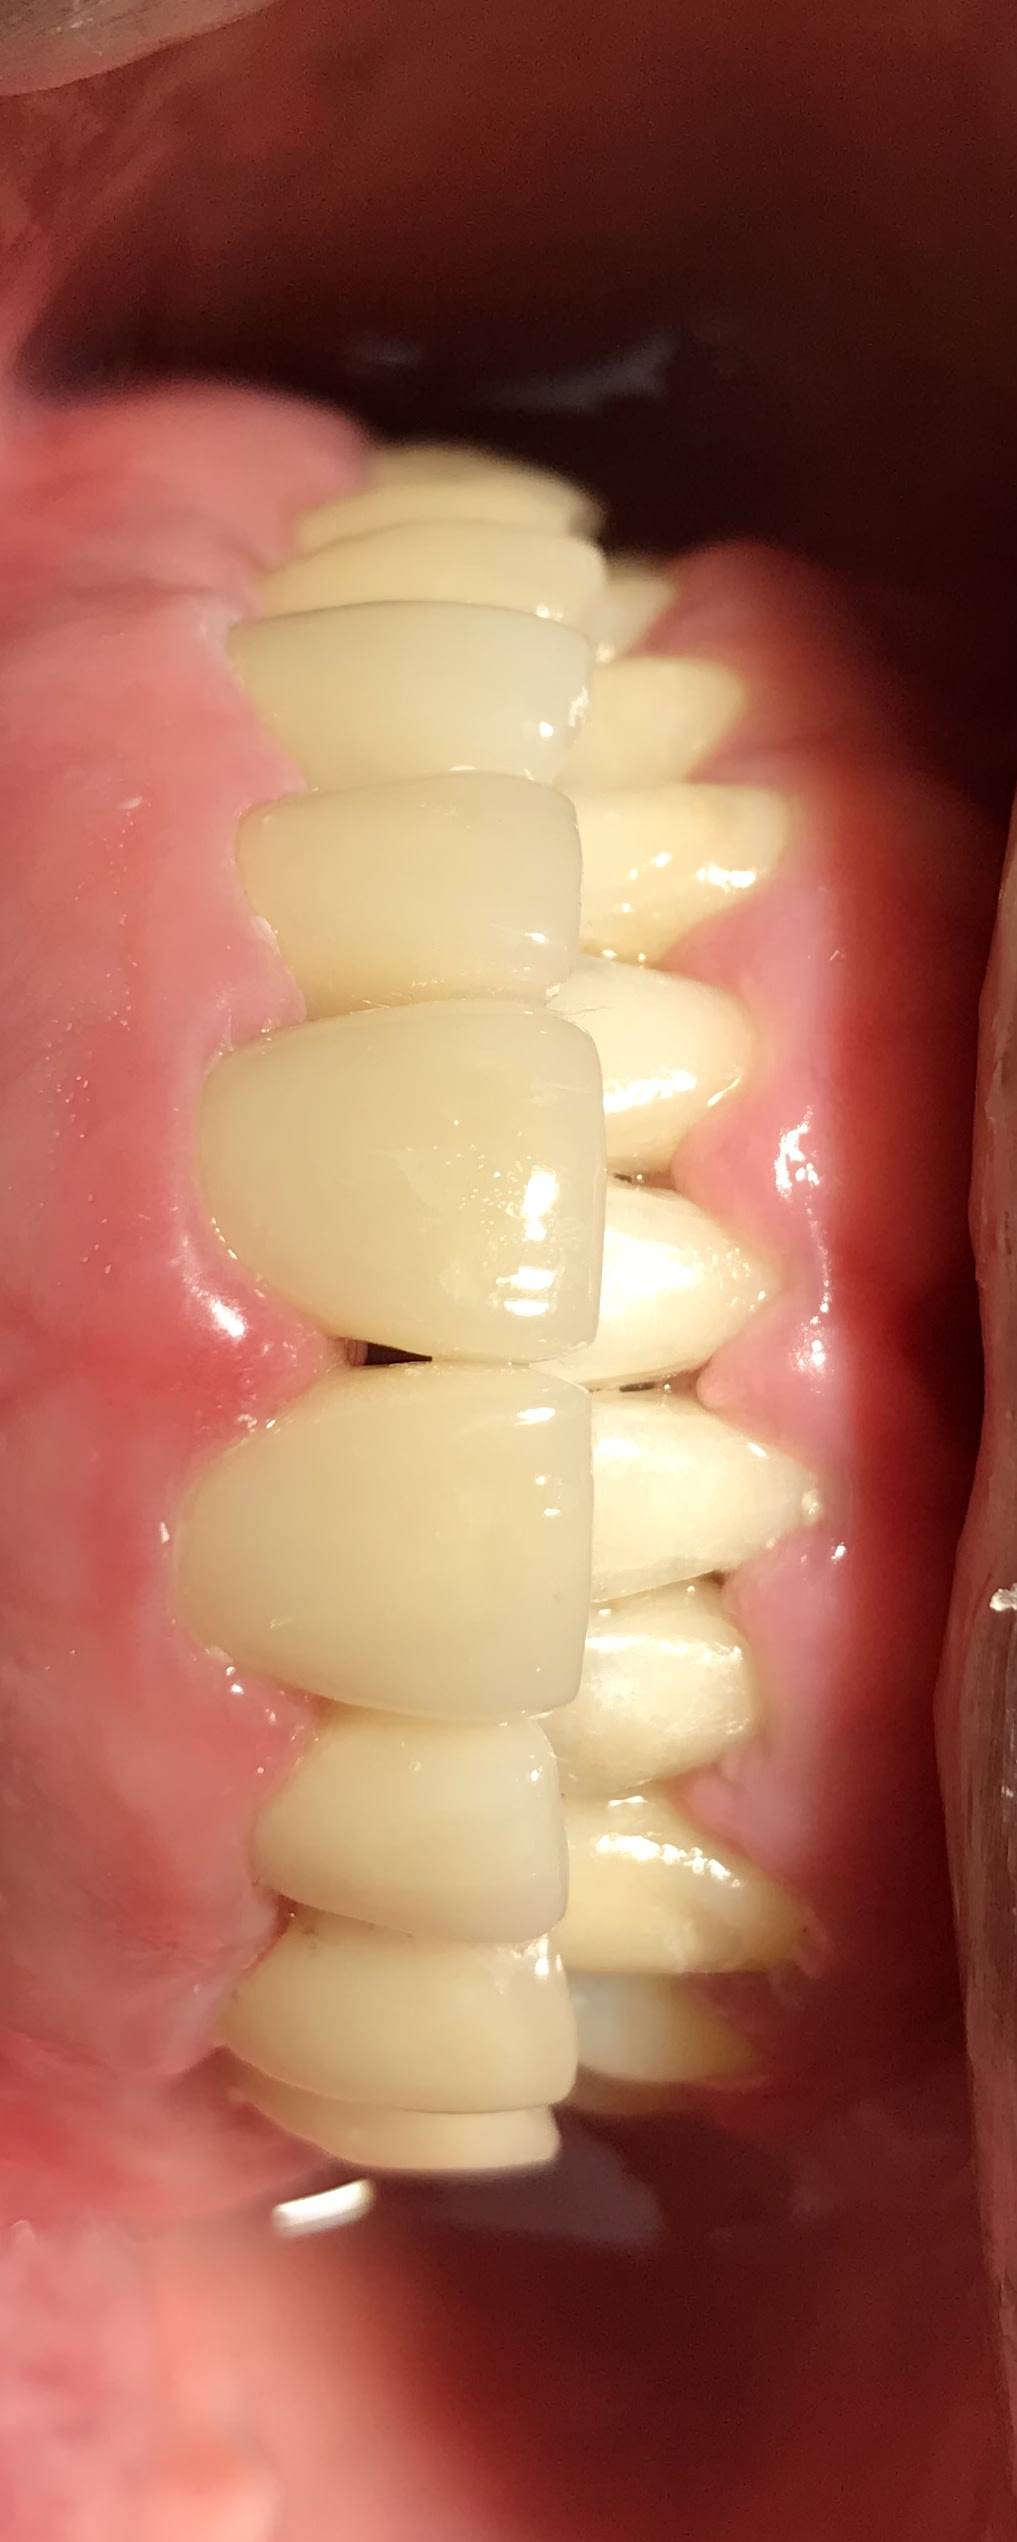

Cas « langue de bovin » terminé

769ebde5 a38e 4211 ba00 1d32b8ee5260 ltw6gn - Eugenol

vulpi

Nan Junior, pour une fois c'est pas une connerie ce que je vais te dire, cas terminé dans 7 à 10 ans si RAS. Avant prudence.

j’espère que dans 10 ans ça sera toujours en place car étant donné le nombre d’implants que j’ai posés ça me ferait bien chier de réintervenir :))

il est propre ton cas fini de la charolaise .

les courbes sont belles , le recouvrement aussi ....

faudrait que tu nous racontes ta stratégie appliquée .